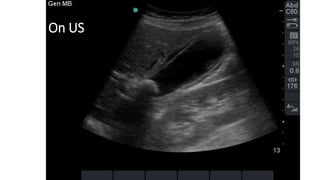

Transabdominal US “diagnostic”

On US

Investigations CBC, LFT, Amylase. AXR:unremarkable. Transabdominal US “diagnostic” HIDA scan